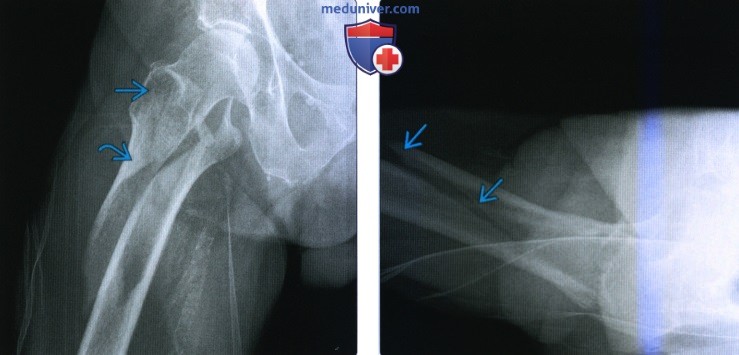

Классификация переломов диафиза бедренной кости: Иллюстрации и информация